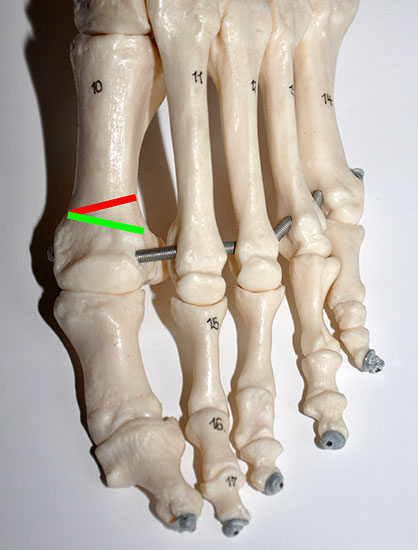

Eine Hallux valgus Fehlstellung besteht typischerweise aus einem erhöhten Intermetatarsale I/II Winkel, einer Adduktion und ggf. Pronation der Großzehe, sowie häufig aus einer Valgusstellung innerhalb der Großzehe (Hallux valgus interphalangeus). Wie bei der klassischen Chevron-Osteotomie erfolgt die Korrektur des erhöhten Intermetatarsalwinkel I/II durch eine Lateralverschiebung des Metatarsale I Kopfes. Ein laterales Release wird transartikulär von dorsal über eine Stichinzision lateral der Strecksehnen durchgeführt.

Die Korrektur eines erhöhten Interphalangealwinkels läßt sich durch eine mediale, schließende Osteotomie der Grundphalanx erreichen (Akin). Die Osteotomieebenen und die Fixation orientieren sich an den offenen Verfahren.

• Korrekturpotential größer als beim offenen Chevron, da die Gelenkkapsel als stabilisierendes Element erhalten bleibt und über eine trikortikale Osteosynthese mit zwei kanülierten Schrauben eine Verschiebung bis ca. 80% des Metatarsaledurchmessers möglich ist (Abb. 1).